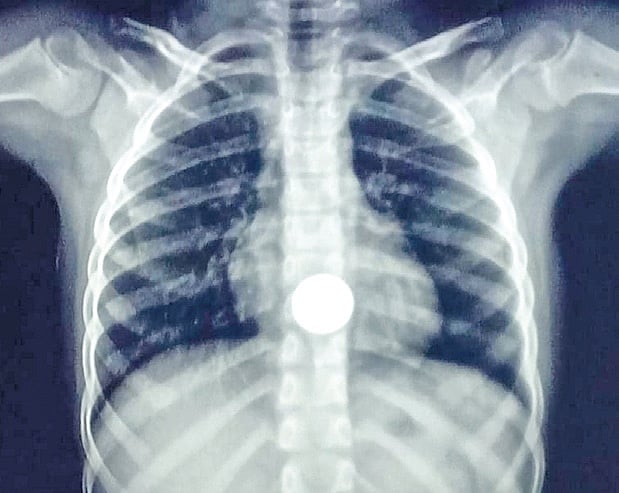

X-ray showing a five-rupee-coin lodged in the seven-year-old girl’s upper esophagus  (Photo | Express)

On examination and after X-ray diagnosis, the doctors there discovered that the coin was lodged in her upper esophagus and was not passing.

According to a release, the girl, who was initially taken to the Musiri government hospital, was referred to MGMGH due to the “critical nature” of her condition. On examination and after X-ray diagnosis, the doctors there discovered that the coin was lodged in her upper esophagus and was not passing.

A team of doctors led by Dr Kannan from the department of surgical gastroenterology soon performed an endoscopy and removed the foreign material from the lower part of the girl’s food pipe. “With swift action, our medical team prevented a potential heart attack. Utilising the endoscopy method, we removed the coin within a three-hour time frame,” the release quoted Dr Kannan.